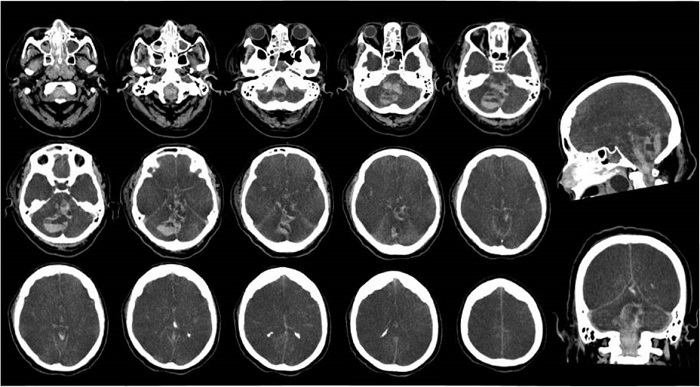

Caso clínico 1. Mujer de 69 años, con antecedente de hipertensión arterial, hipotiroidismo en suplencia y diabetes mellitus tipo II no insulinorequirriente, con cuadro clínico de quince días de fiebre no cuantificada, tos no productiva, disgeusia, anosmia, odinofagia y disnea de esfuerzo siete días después del inicio de los síntomas. Evoluciona a síndrome de dificultad respiratoria aguda (SDRA) severo, hipoxemia refractaria con trastorno de oxigenación severo (PAFI 60), con requerimiento de ventilación mecánica invasiva controlado por volumen, vasopresor e inotrópico (noradrenalina y dobutamina titulable), en contexto de neumonía grave de origen viral por SARS-CoV-2 confirmado. Se encuentran marcadores de severidad elevados (lactato deshidrogenasa 1575, proteína c reactiva 26, ferritina 2000, troponina 1344, dímero D > 10 000, leucocitosis 21 080 y linfopenia 2100), y reporte de tomografía de tórax simple con opacidades alveolares con patrón de vidrio esmerilado difusas en ambos campos pulmonares, con consolidaciones subpleurales posteriores de predominio en lóbulos inferiores. Progresa a falla renal aguda KDIGO ni, de etiología multifactorial en terapia de reemplazo renal con hemodiálisis. Recibe manejo con dexametasona, anticoagulación plena con enoxaparina, antibioticoterapia con cefepime, ciclos de pronación y sedación con propofol 10 mg hora y dexmedetomidina 0,5 mcg kg hora. Durante evolución presenta falla multiorgánica, síndrome coronario agudo, epistaxis, sangrado oral y vaginal, así como trombocitopenia 55 000, por lo que se suspende anticoagulación. Para el día diez de hospitalización en uci, durante retiro de sedación presenta deterioro neurológico, dado por presencia de midriasis arreactiva, reflejos de tallo ausente con bradicardia e hipotensión, por lo que fallece. Se realiza tomografía de cráneo simple con evidencia de hematoma retrovermiano que se extiende al hemisferio cerebeloso derecho, con un volumen aproximado de 46 cc (véase la Figura 1).

Caso clínico 2. Paciente masculino de 34 años remitido de San Buenaventura, Valle del Cauca, sin antecedentes conocidos. Ingresó después de cinco días de astenia, tos con abundante expectoración blanquecina, fiebre subjetiva, con posterior disnea progresiva asociada a hipoxemia en contexto de enfermedad SARS-C0V-2/ COVID-19 con falla ventilatoria, severo compromiso radiológico; recibe manejo con hidroxicloroquina, lopinavir, ritonavir, vancomicina, piperacilina/tazobactam y claritromicina. Durante evolución presenta parada cardíaca por actividad eléctrica sin pulso (AESP), posterior a lo cual documentan mioclonías cara y tronco. por lo que tratan con levetiracetam. Tomografía de cráneo simple evidenció edema cerebral y hemorragia subaracnoidea difusa con descenso amigdalino (véase la Figura 2), por lo cual se realizan medidas antiedema con solución salina hipertónica y sedación profunda con midazolam. Presenta complicaciones de SDRA severo en fase fibrótica con secuelas neurológicas en relación con encefalopatía hipóxico-isquémica, en estado de mínima conciencia y requerimiento de gastrostomía y traqueostomía. En el momento, paciente en seguimiento en controles por neurología, sin nuevas complicaciones ni procesos infecciosos a la fecha, dependiente funcional.